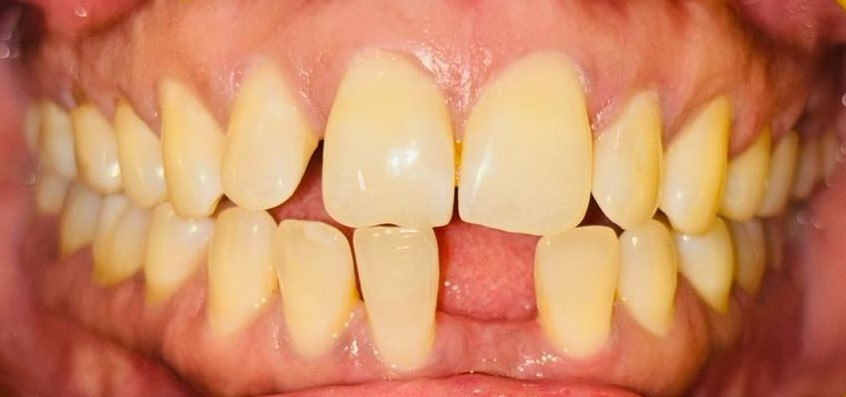

Before Before